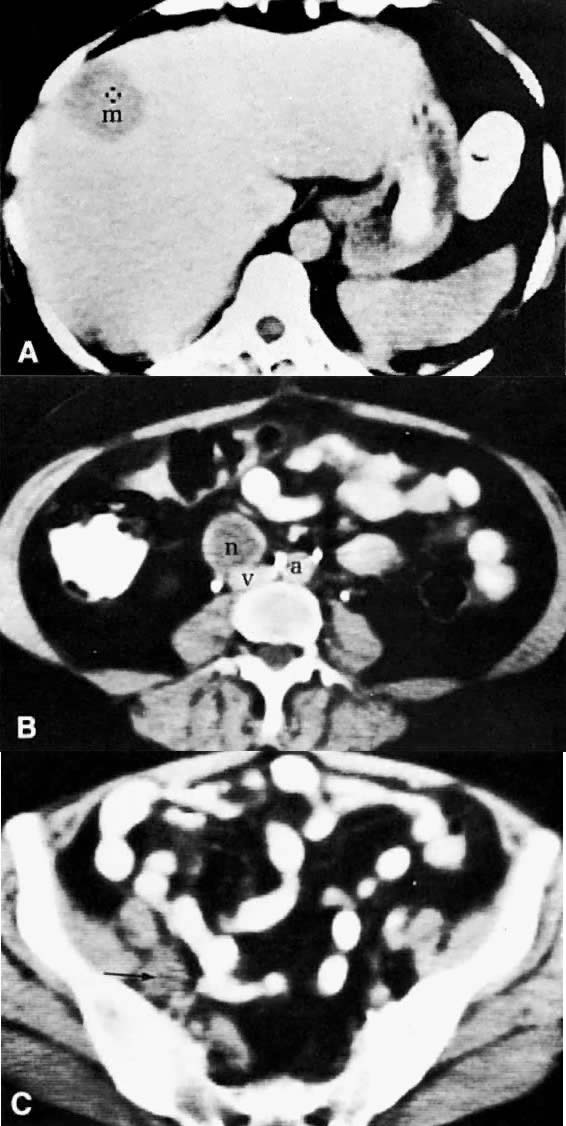

Metastatic granulosa cell tumor. A. CT scan of the upper abdomen shows a low-density, well-marginated mass (m) in the right lobe of the liver. B. Lower abdominal CT scan shows a necrotic paracaval mass (n) consistent with lymphadenopathy. C. CT scan of the pelvis shows an enlarged right external iliac lymph node (arrow) measuring 1.5 cm in diameter with some necrotic changes seen in its center. (a, aorta; v, inferior vena cava.)